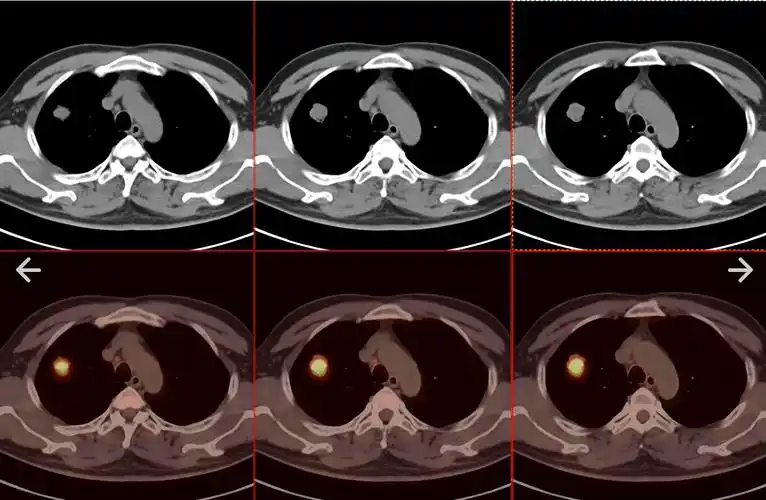

petct病例(8):发现肺结节不重视,造成悲剧,巫医生也很痛心_检查_进行